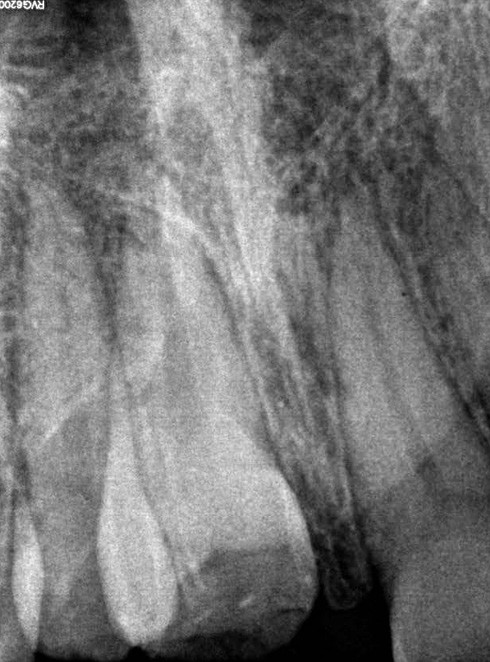

Yasmine, une adolescente de 14 ans et demi, en bonne santé générale, consulte en urgence vers 10h30, à la suite d’une chute s’étant produite le matin même en allant à l’école vers 8h. Les figures 1 et 2 montrent respectivement les vues cliniques et radiographiques. La mère nous rapporte un antécédent de trauma sur les incisives centrales, il y a quelques années.